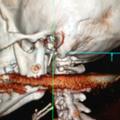

Mož s harpuno ustrelil ženo v usta

Neko Brazilko je mož med čiščenjem harpune ponesreči ustrelil in jo zadel v usta. Harpuna je prebila njeno hrbtenico, a…